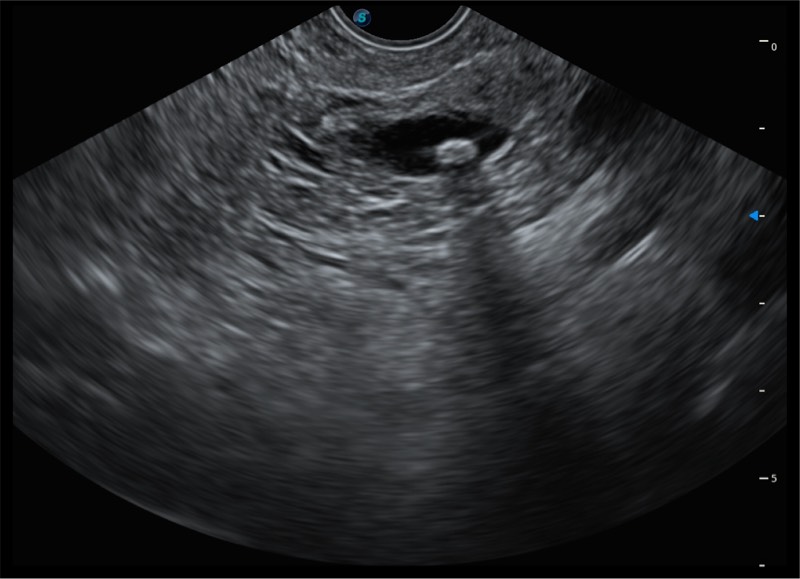

搭载百万级CMOS成像技术

及自主研发凸阵换能器,

可呈现优质的内镜和超声画面

基于二十年的超声技术积累,16877太阳集团提供了最新一代的独立超声主机,在提供高质量图像的同时满足多学科使用。具备常见多普勒技术并提供弹性成像、声学造影等高端影像技术。新一代传感器具有更强的抗干扰能力并减少图像伪影。

150°超声扫描角度

4-12MHZ宽频输出